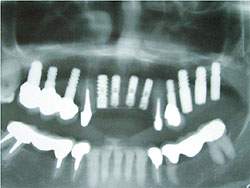

AQBは、結晶体の密度が高く純度も高いことが特長であり、三井記念病院におけるAQBインプラント症例では、最長18年を経過した臨床例においても、歯槽骨の状態は変わらず、逆に密になっていることが分かっている。そこで、上顎臼歯部の骨吸収症例において、サイナスリフトと同時にAQBインプラント1ピースを植立し、自家骨移植や人工骨移植を行わず、治療を行った症例を報告した。6例に施行し、全例、予後良好で、すべて植立後4ヵ月以内で咬合を開始した。GBR症例においてもAQBインプラント2ピースを埋入し、自家骨移植や人工骨移植は行わず、チタン入り非吸収性膜を用いたスペースメーキングを行った。その結果、4ヵ月後には歯槽骨の再生を確認した。

| AQBを用いて歯槽骨再生を図った症例 | |

サイナスリフト症例 ▼ ![]() 術前 ![]() 術直後 ![]() 術後4ヵ月 |